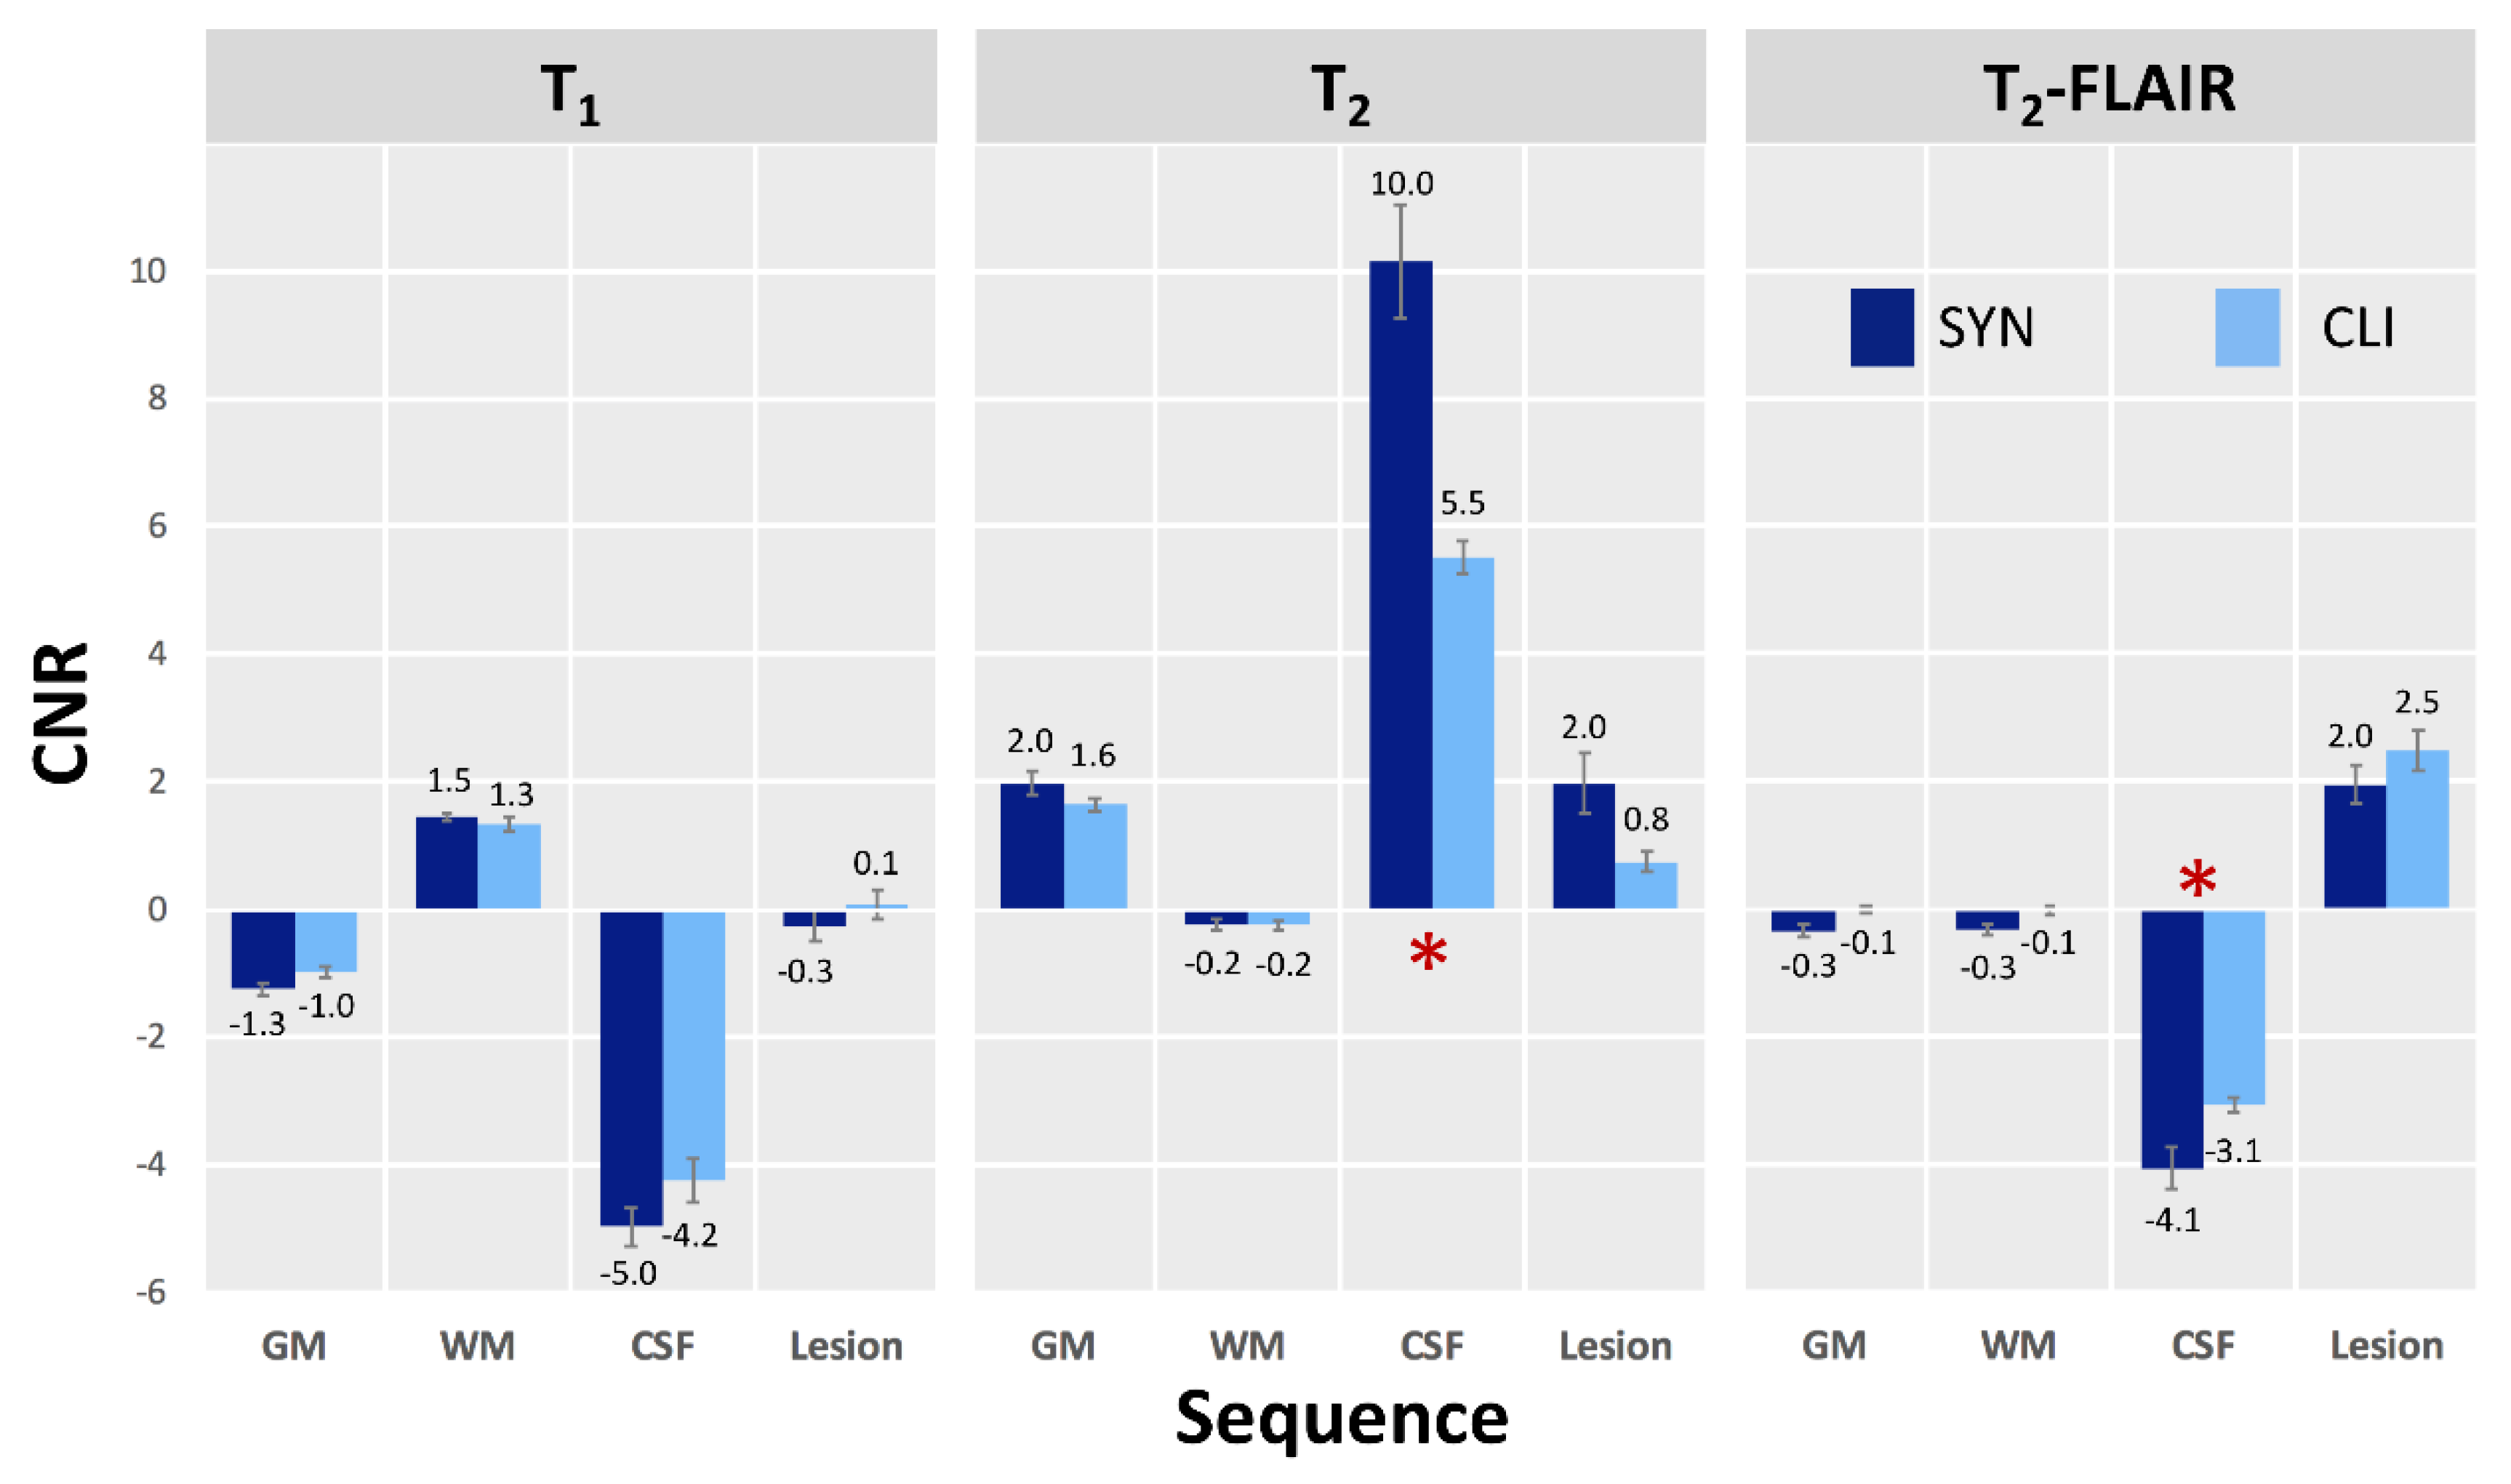

3.2. Participant Evaluation